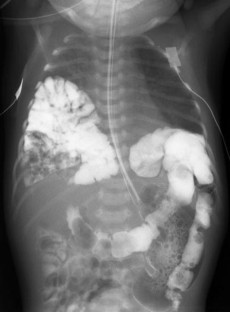

Fig. 1

Fig. 2